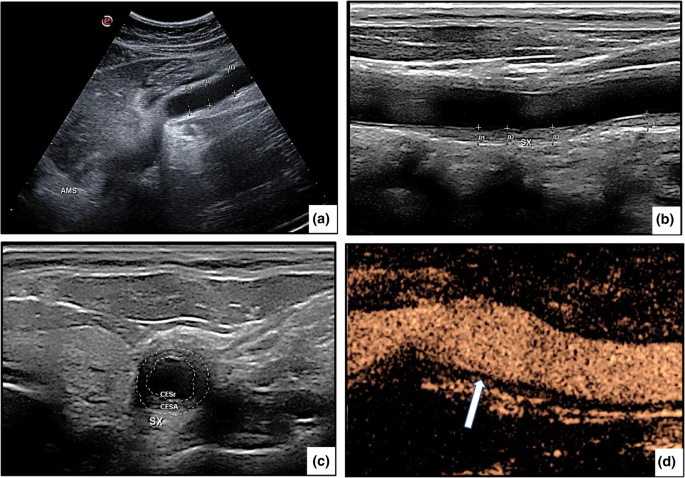

Ocular manifestations were detected in 16 of our patients (37.2%), usually late in the course of the disease, and were frequently responsible for severe visual deterioration. These patients are described in detail in a separate report (Dammacco R et al., submitted for publication). Musculoskeletal and neurological features were less frequent, but not rarely were the presenting symptoms of the disease. Renovascular hypertension, often associated with proteinuria and microhematuria, was a prominent manifestation, detected in 7 of the 9 patients with type V TAK and in 2 patients with type IV TAK. Dermatologic findings, mostly erythema nodosum, and abdominal symptoms indicative of gastrointestinal involvement (Fig. 1A) were detected in a minority of patients. A comparative analysis of the clinical findings according to sex showed that constitutional and cardiovascular features were more frequent in female patients, whereas ocular manifestations were diagnosed in a larger number of male patients. The differences, however, were not statistically significant (Table 1).

Fig. 1

figure 1

a A 33-year-old woman with type III Takayasu arteritis complained of abdominal pain, nausea, vomiting, and diarrhea. A B-mode ultrasound showed the rare finding of superior mesenteric artery aneurysm. The diagnosis of “superior mesenteric artery syndrome” was considered. b B-mode ultrasound image of the right common carotid artery in a 27-year-old man diagnosed with type IIa Takayasu arteritis. Longitudinal B-mode ultrasound shows mid-echoic, homogeneous circumferential wall thickening (“macaroni sign”). The thickness of the intima–media is between 1.3 and 2.0 mm (normal value ≤ 0.9 mm). c A transverse scan of the same vessel shows marked, concentric, hypoechoic wall thickening that reduces the lumen by > 50%. d Contrast-enhanced ultrasound of the carotid artery allows to detect a high uptake of microbubbles, indicating active disease

The most widely used of these techniques was high-resolution color Doppler ultrasonography (CDUS), performed in all patients. Among the findings were a homogeneous, hypo-echogenic, circumferential thickening of the arterial wall affecting to a variable extent and in variable combinations the carotid, subclavian, axillary, and vertebral arteries, either mono- or bilaterally, as well as the abdominal aorta. In several instances, ultrasonography showed a characteristic circumferential thickening of the intima–media complex, a pattern referred to as the “macaroni sign” [12, 28] (Fig. 1B, C) and considered pathognomonic for TAK [29]. Other advantages of CDUS, in addition to its ability to assess intima–media thickness, are the absence of radiation exposure and the easy repetition of the imaging study [30]. However, the technique is operator dependent and unable to accurately image the aortic arch and descending aorta. A more reliable assessment is provided by contrast-enhanced ultrasonography (CEUS), which is more sensitive than serum measurements of acute-phase reactants, such as ESR and CRP, in the monitoring of disease activity and the response to therapy (Fig. 1D) [31, 32].